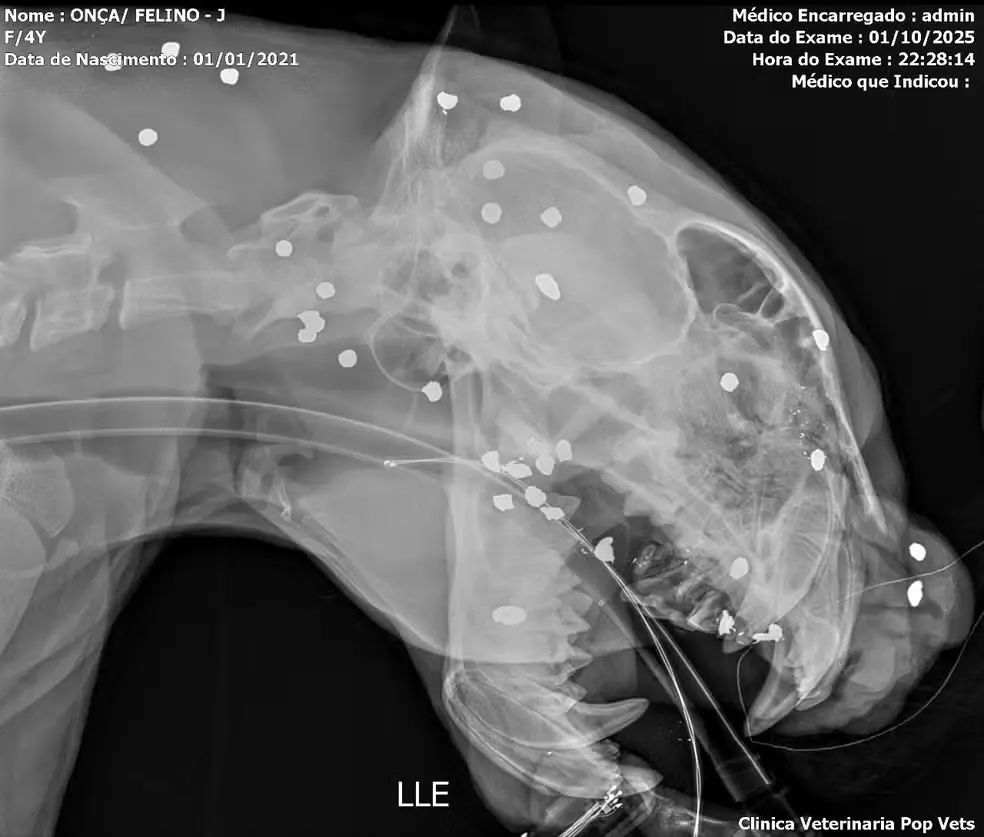

A onça-pintada resgatada no Rio Negro, próximo ao Complexo Turístico da Ponta Negra, continua sob cuidados médicos após ser alvejada com mais de 30 projéteis. O felino, um macho de 54 quilos e 1,78 metro de comprimento, foi encontrado exausto e com ferimentos graves, incluindo dentes quebrados e um olho bastante afetado, embora o inchaço já esteja diminuindo, segundo a equipe de biólogos e veterinários que acompanha sua recuperação.

Raio-x mostra mais de 30 marcas de tiros no rosto de onça resgatada após passar horas a deriva em rio no AM. Foto: Reprodução